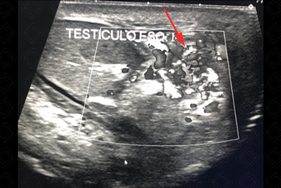

Descrição das figuras: Ultrassonografia da bolsa escrotal. Epidídimo esquerdo com volume muito aumentado e com hipervascularização ao Doppler colorido, compatível com epididimite aguda à esquerda.

• Ultrassonografia da bolsa escrotal: o epidídimo apresenta volume aumentado, sua ecogenicidade pode estar aumentada ou reduzida, mas em geral sempre heterogêneo e com fluxo aumentado no estudo com Doppler colorido. Edema de bolsa escrotal e uma hidrocele reacional comumente estão presentes. A inflamação pode atingir o testículo por contiguidade, levando a um quadro de orquiepididimite (figuras acima). Exame de escolha para população pediátrica ou adulta.